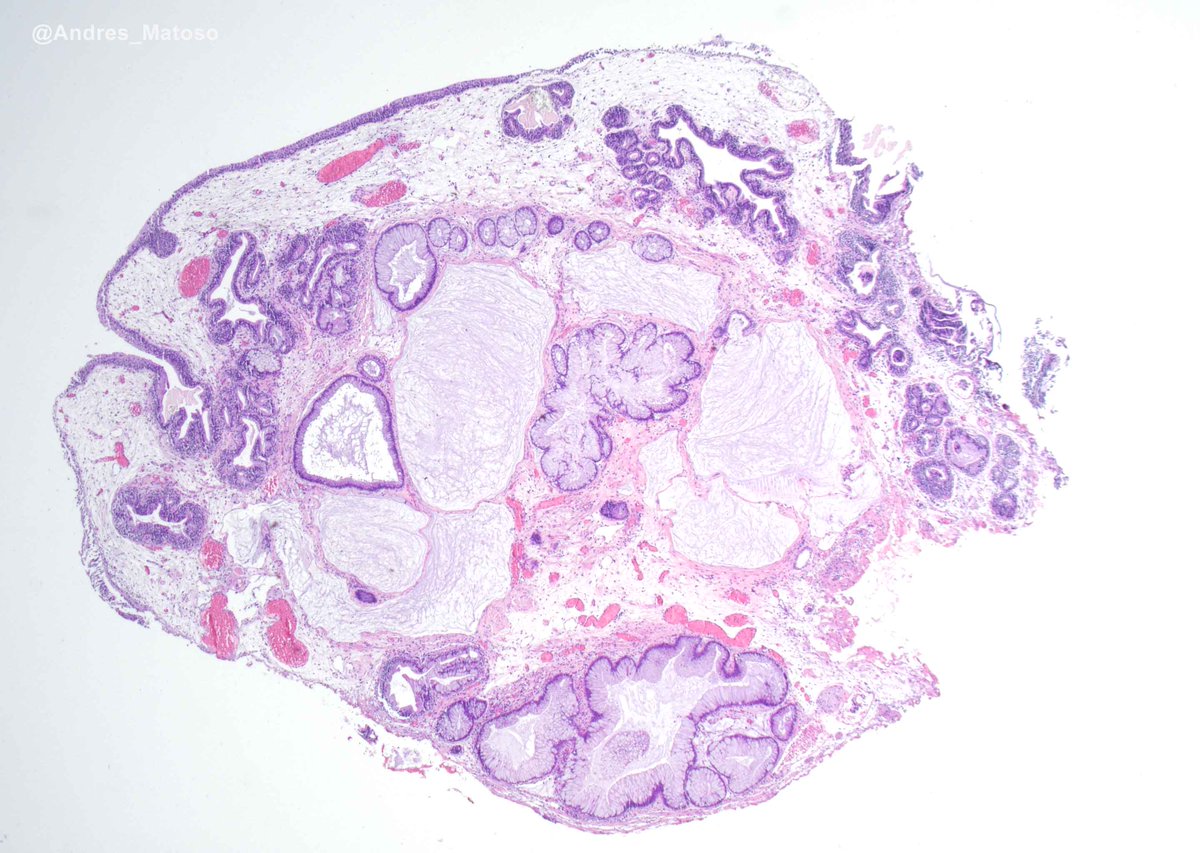

40s M 30 cm thigh mass, multilocular cystic on imaging. Dx/IHC?? 8 H&E images below.

#BSTpath #PathTwitter #PathX